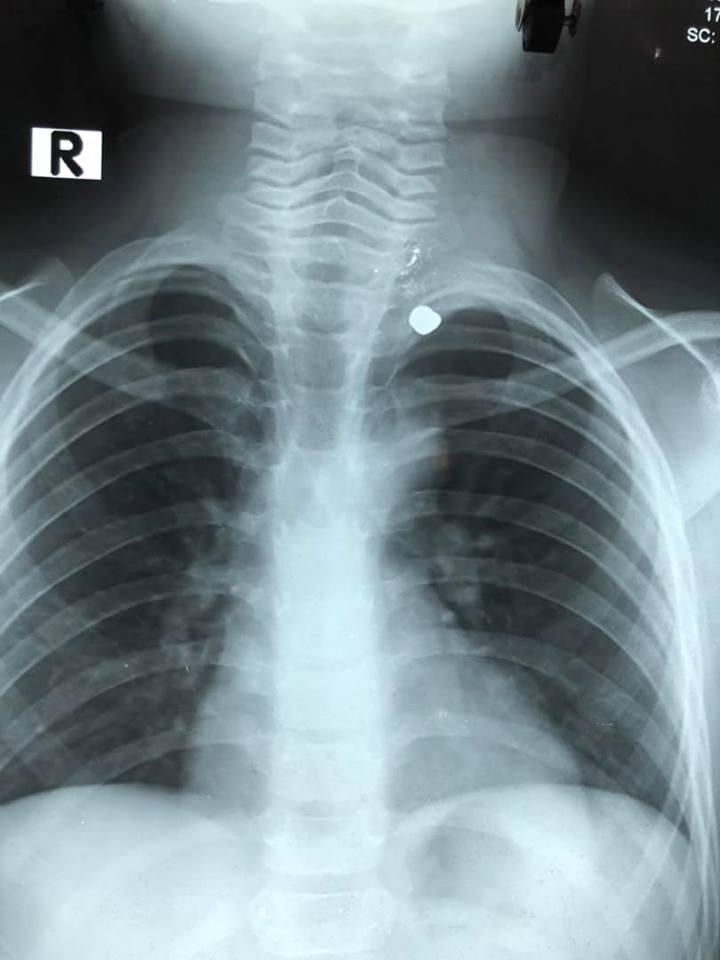

Tại khoa cấp cứu bệnh nhân được thăm khám, chụp X Quang ngực.

Hình viên đạn nằm trong lồng ngực nạn nhân.

Ghi nhận lúc phẫu thuật, viên đạn nằm ở đỉnh phổi trái, cạnh bên động mạch dưới đòn trái, may mắn mạch máu lớn và thần kinh không bị tổn thương.